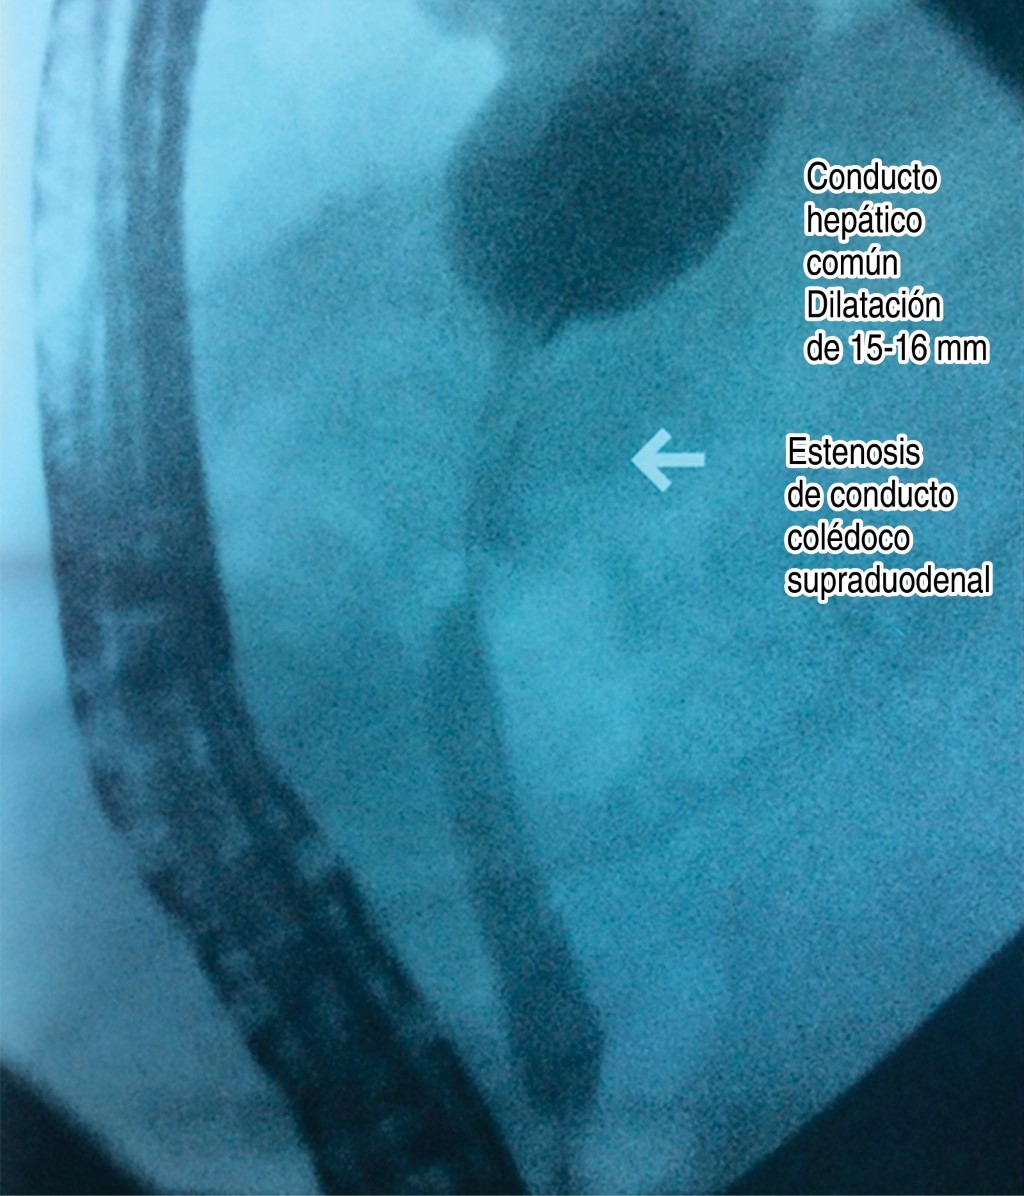

Por los hallazgos en la TC se decide realizar colangiopancreatografía retrógrada endoscópica (CPRE) que informa lo siguiente (Figura 3): "ámpula de Vater pequeña, con ectropión del ámpula, drenaje biliar nulo. Vías biliares intrahepáticas con dilatación severa. Vías biliares extrahepáticas con dilatación de conducto hepático común de entre 15-16 mm, se observa zona de estrechez en punta de lápiz a nivel de la porción supraduodenal, con aproximadamente 2 cm de longitud, drenaje biliar nulo. Se realiza esfinterotomía selectiva de la vía biliar, obteniendo salida de abundante material purulento y detritus celulares. Se coloca endoprótesis. Conclusión: dilatación de vías biliares intrahepáticas, tumor de Klatskin tipo IV, colangitis."

Figura 3